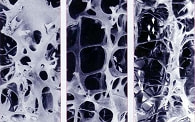

X線検査では、関節およびその組織の腫脹と関節周囲の

骨粗鬆症がまず出現します。しかし、はじめのうちはそれ以上の骨の変化はみられません。

ただし炎症が続くと、関節付近の骨が「虫喰い」のように欠けてきます。これを専門的には「 骨びらん」とよぴます。さらに進行すると、関節の隙間が狭くなり、骨同士が融合する 「 骨強直」などがみられます。CTおよびMRI検査は、頚椎の病変や大腿骨頭の病変をみる場合にとても役立ちます。